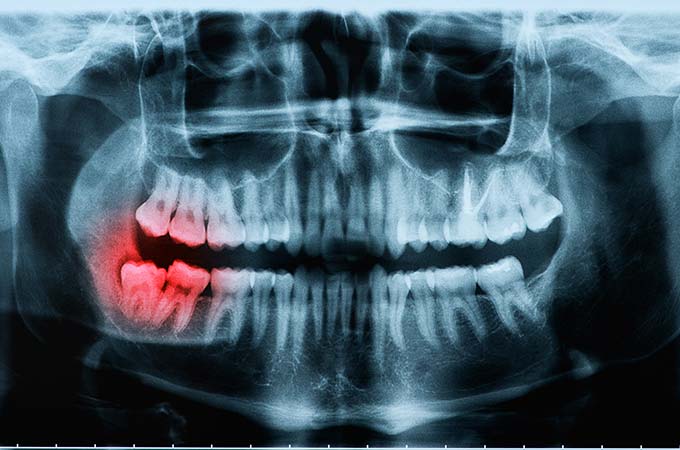

Dr. Shalaby will take an X-ray of the area to help plan the best way to remove the tooth.

Wisdom teeth don’t normally appear until after all or most of an adult’s teeth have come through and sometimes there just isn’t enough room for any more teeth. This impedes the growth of the wisdom teeth and they can become impacted. Impacted wisdom teeth can become infected or even damage the teeth next to them. If this happens then a dentist will recommend that the wisdom teeth are removed. This is often carried out by a surgical procedure, because wisdom teeth are often hard to access or under the gum line.